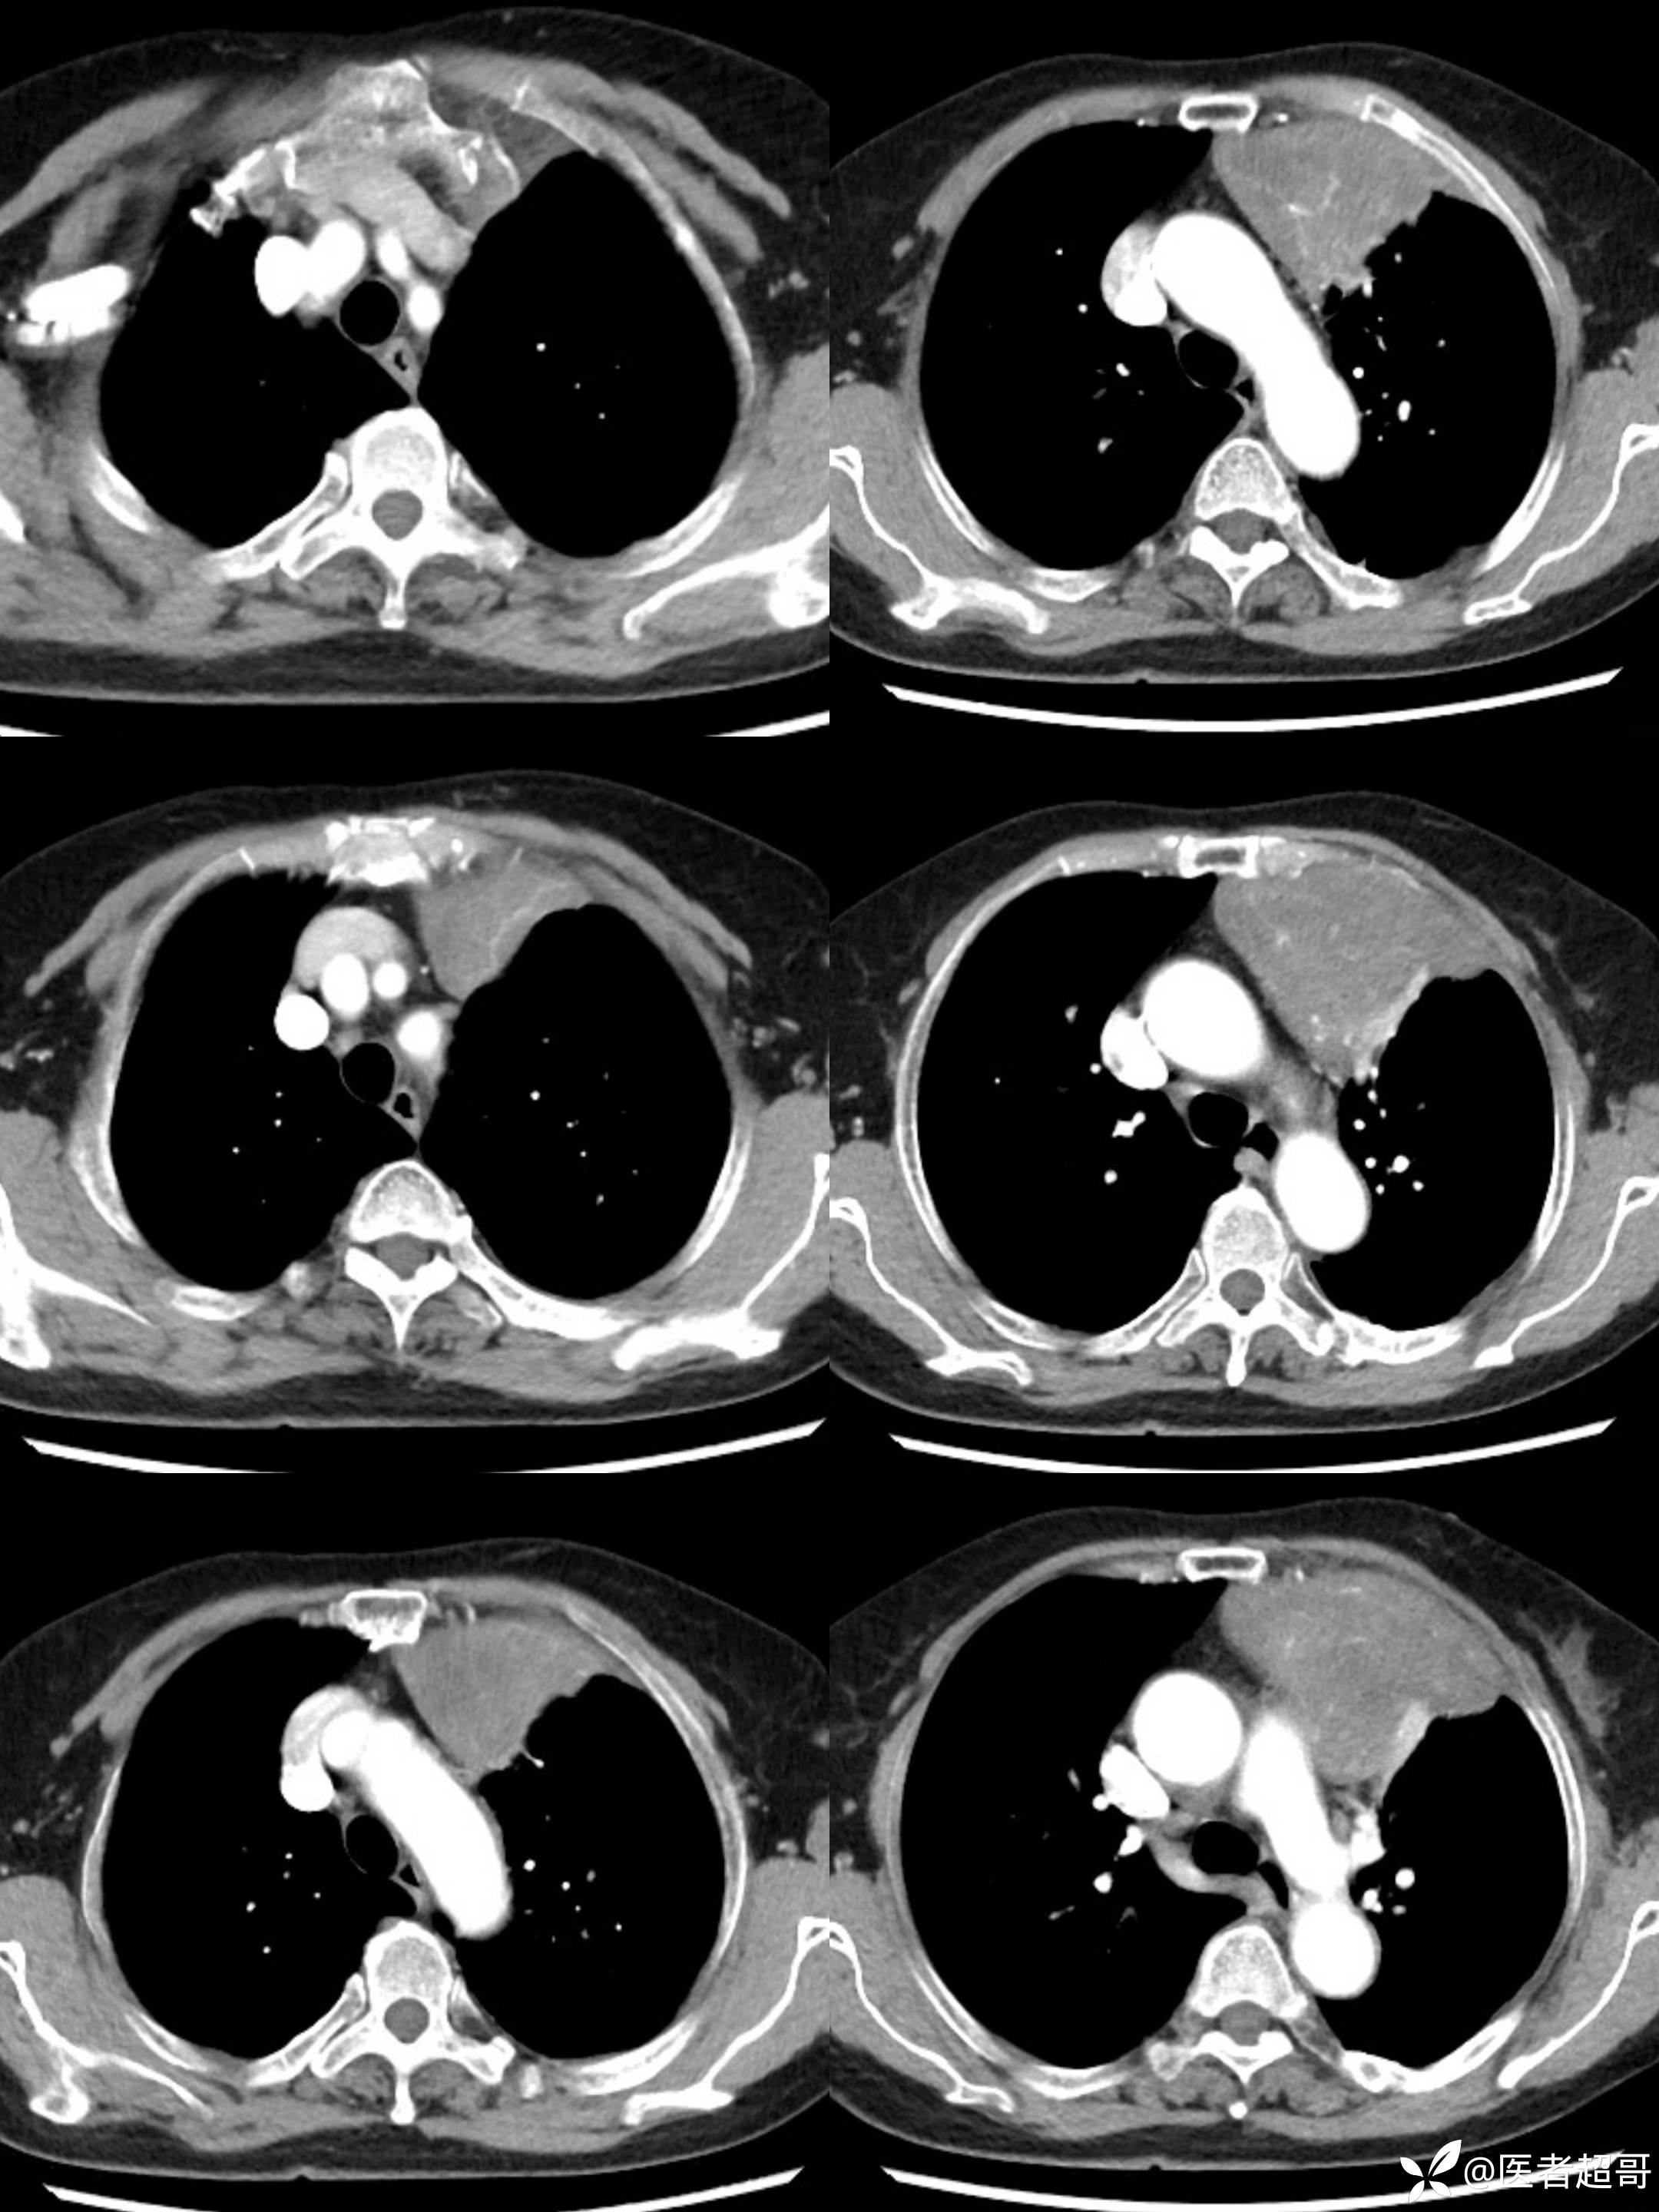

女73岁,体检发现左上纵隔占位1周

患者于1周前体检行CT检查提示:“左上纵隔见不规则团块状软组织密度影,大小约90*63mm”,患者平素偶有头晕,无明显胸闷气急,今为进一步治疗来我院就诊, 门诊以"左上纵隔肿物"收入院。

糖类抗原125(CA125):44.9(正常0-30.2),余实验室检查无殊